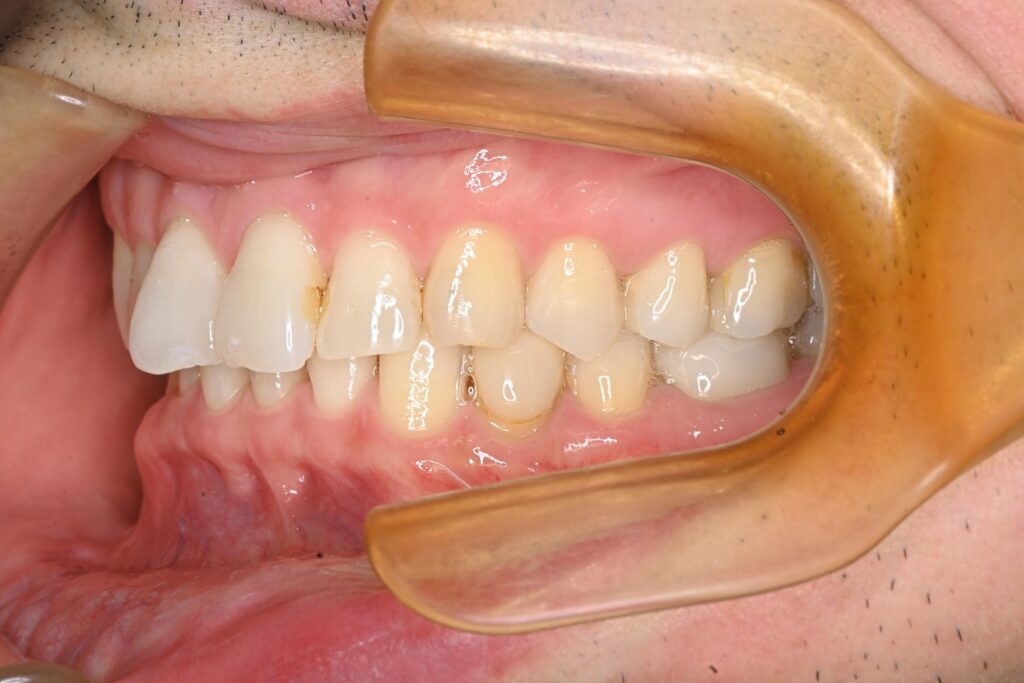

After

治療結果

全ての金属を非金属素材に置き換え、感染源も除去した結果、治療後は症状が落ち着いている状態が確認されました。 患者様はアレルギーやそれに伴う症状の悩みが大幅に軽減されたようで、非常に喜んでいただけました。